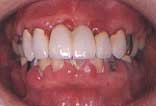

| 初診時 口腔内写真 | 1か月後 | 2年後 | 投薬後1か月 |

徹底的に歯石除去したけれど… | メインテナンスの甲斐なく歯肉腫脹 | 歯肉状態大幅に改善 |

初診より約2年経過した時点で、折りしも“アムホテリシンBシロップの効果”が新聞上で公表

され何かと話題になった時期だったこともあり、アムホテリシンBシロップのうがいを試みる

こととした。

アムホテリシンBシロップ投薬後1か月時点での歯肉回復は、かなり著明であった。

考察:

「歯周疾患の原因がカンジダ菌による」とは思っていないが、歯石除去を始めとした通常の

処置を行っても改善しない重傷(難治性)の歯肉炎の場合には、少なからずカンジダ菌が

関与している症例があると思われる。